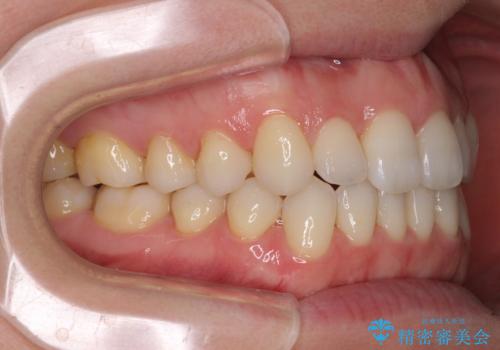

前歯の叢生とオープンバイト インビザラインでの矯正治療

- 前歯の開咬を気にして来院された患者様です。

開咬の治療は、前歯を閉じるように動かすとともに、上下臼歯を圧下(骨内にめり込ませる)させることで進めて行きます。

インビザラインは臼歯の圧下を効果的に行えるため、インビザラインを用いて矯正治療を行うこととしました。

オープンバイトは舌の突出癖により誘発され、治療後も突出癖が残っている容易に後戻りしてしまいます。

治療期間を短縮するためにも、舌突出癖の改善が極めて重要となります。